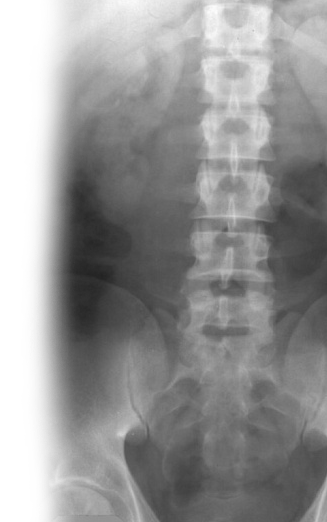

Рентгенография почек и мочевыводящих путей – важный метод визуализации почек, мочеточников и мочевого пузыря.

С помощью рентгенографии определяется положение почек, определяется наличие камней в мочевыделительной системе.